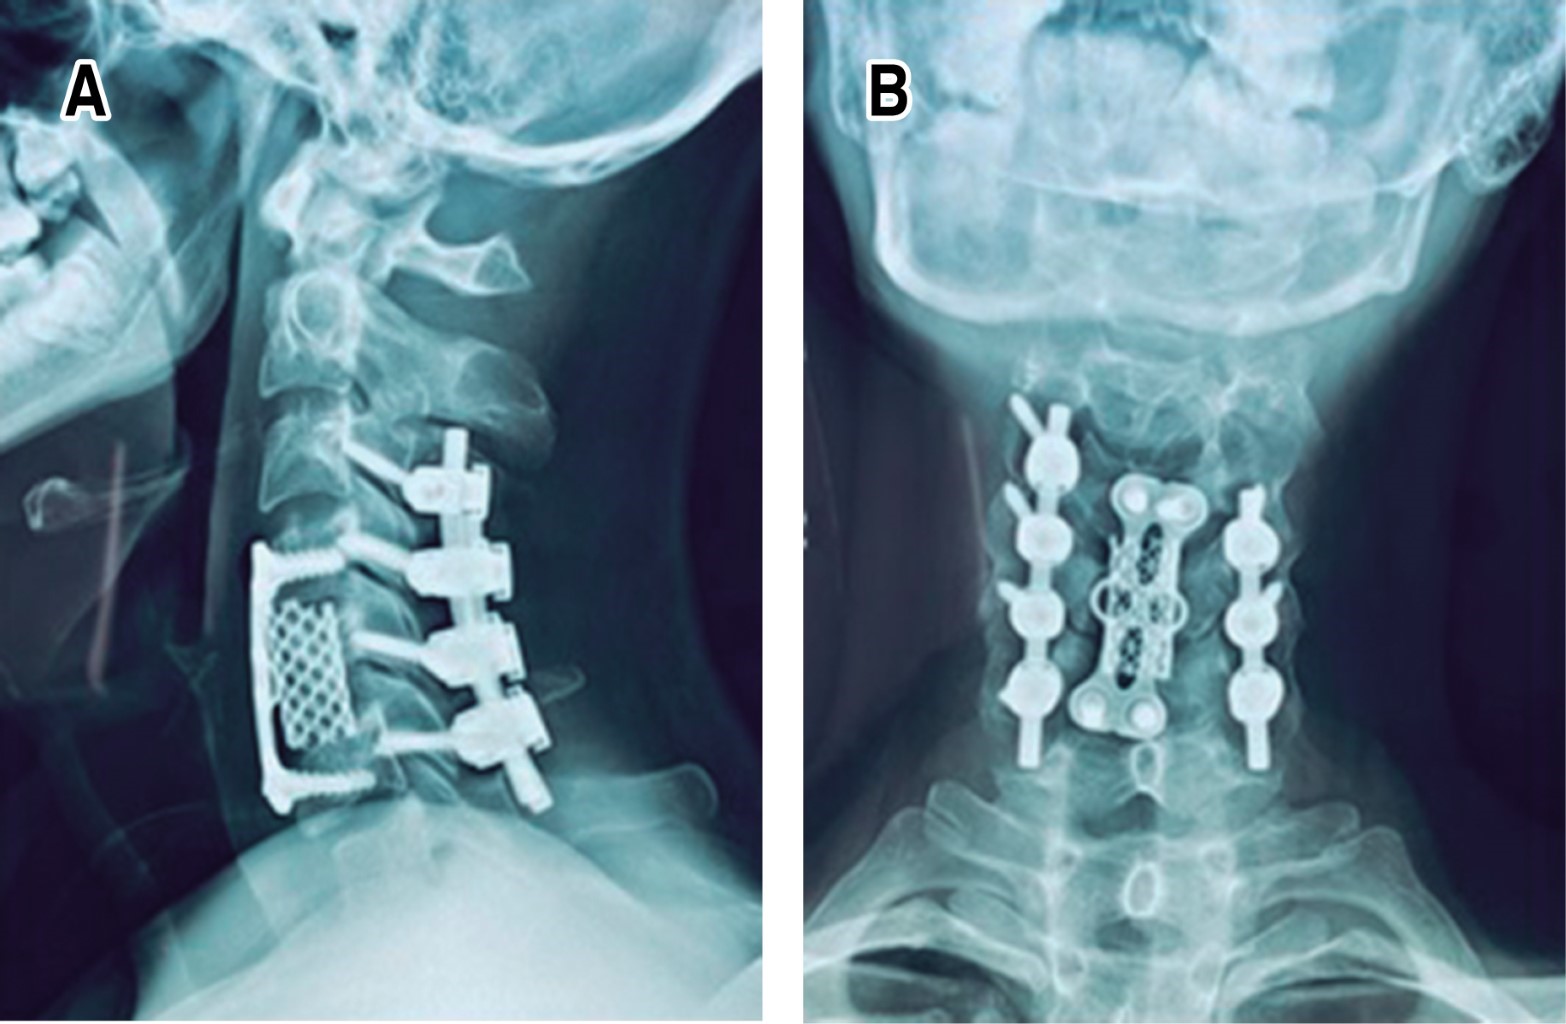

A los siete días después de su lesión, en primer orden se realiza el abordaje posterior con estabilización a masas laterales C4-C5 C5-C6, laminectomía C5-C6 y artrodesis posterolateral; se procede a efectuar un abordaje anterior con discectomía C5-C6 más fusión con caja intersomática tipo PEEK C5-C6 y placa anterior cervical, con una duración quirúrgica de tres horas 30 minutos para ambos abordajes y un sangrado reportado de 350 mililitros (Figura 2).

Ingresa para tratamiento quirúrgico con doble abordaje cervical en un solo tiempo quirúrgico. Se realiza un abordaje cervical posterior con estabilización a masas laterales C5-C7 e instrumentación transpedicular T2, laminectomía C6-C7, artrodesis posterolateral y, posteriormente, con la paciente en decúbito supino, se efectúa un abordaje cervical anterior con discectomía C6-C7 más fusión con caja intersomática PEEK C6-C7 y colocación de placa cervical anterior. La duración de la cirugía fue de cinco horas 45 minutos y un sangrado reportado de 600 mililitros (Figura 4).

Ingresa para tratamiento quirúrgico de urgencia en medio particular el 02/11/2021, dentro de las primeras 24 horas posteriores a la lesión, con doble abordaje en un solo tiempo quirúrgico y se inicia con un abordaje cervical posterior para la estabilización a masas laterales C3 a C6 (masa lateral C6 izquierda, al momento de la cirugía se observa fracturada y no realiza estabilización en dicha región) con laminectomía C5-C6 y artrodesis posterolateral. Se procede a colocar al paciente en de cubito supino para continuar con un abordaje cervical anterior, se realiza corpectomía C5, colocación de malla de titanio en C5 y placa cervical anterior C4-C6, con tiempo quirúrgico total de tres horas 30 minutos y un sangrado de 300 mililitros (Figura 6).